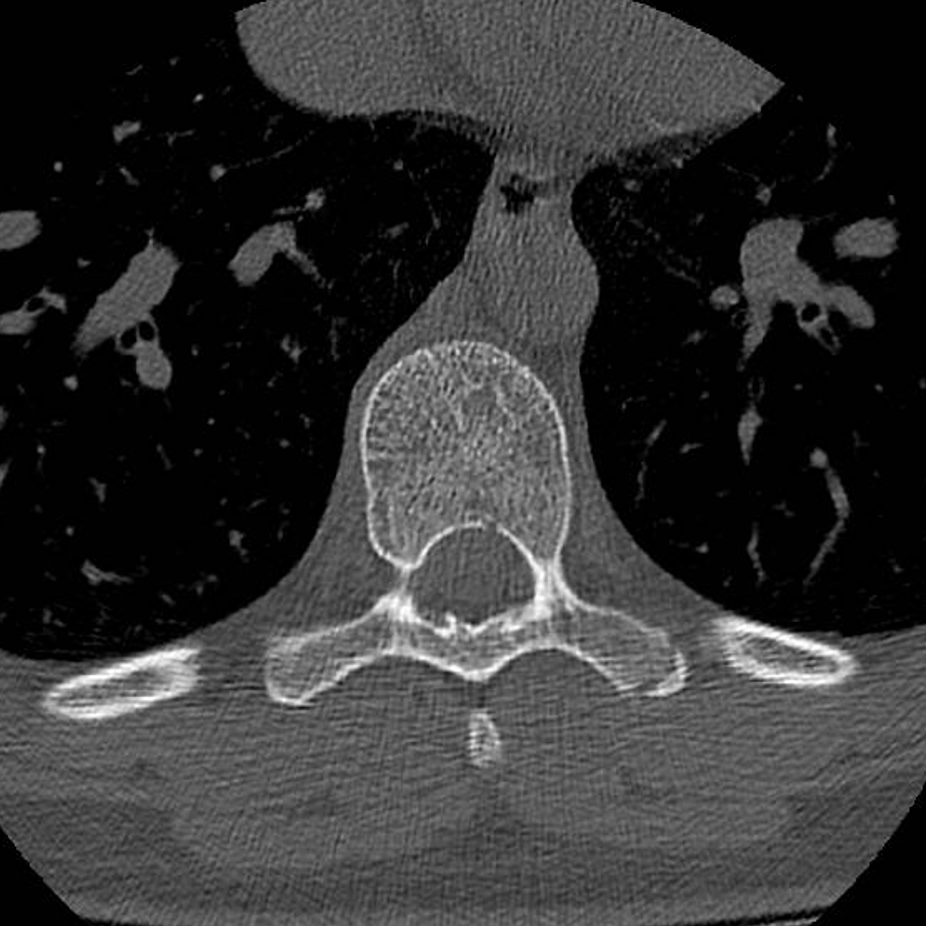

Young gentleman came with severe low back ache following an episode of dengue fever. What do we see here? #spineimaging #medtwitter #radtwitter #FOAMrad #neuroimaging @drvenkimdrd

DrYevSam_Rad's tweet image. Young gentleman came with severe low back ache following an episode of dengue fever. What do we see here?